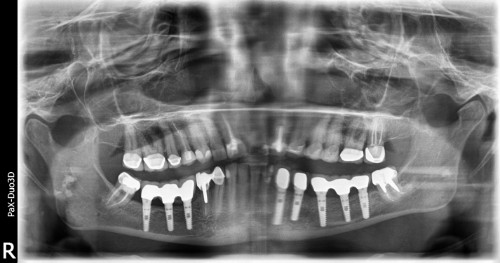

The inferior alveolar nerve, which gives feeling to the lower lip and chin, may need to be moved in order to make room for the placement of dental implants in the lower jaw. A nerve repositioning procedure is limited to the lower jaw and may be indicated when teeth are missing in the area of the two back molars and/or second premolars. This procedure is considered a very aggressive approach since there is almost always some postoperative numbness of the lower lip and jaw area, which typically dissipates very slowly, but may be permanent. Usually other, less aggressive options are considered first (placement of blade implants, etc).

Typically, we remove an outer section of the cheek on the side of the lower jaw bone in order to expose the nerve and vessel canal. We then isolate the nerve and vessel bundle in that area and slightly pull it out to the side. We then place the implants while tracking the neuro-vascular bundle. Then the bundle is released and placed back over the implants. The surgical access is refilled with bone graft material of the surgeon’s choice and the area is closed.